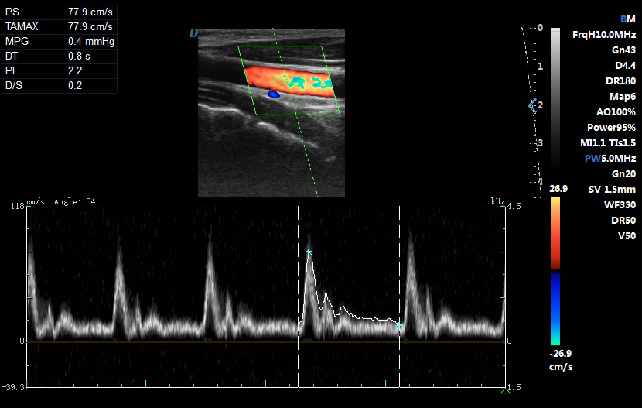

Automatic Spectrum Tracking Measurement Technology

Ultrasound Doppler technology is used in the ultrasound system for examining the heart and arteries and veins. It is necessary to extract relevant parameters from the Doppler spectrogram to evaluate the hemodynamic status of the heart and blood vessels. The disadvantage of manual detection is that the operator’s marking of the peak velocity is

relatively monotonous and time-consuming, with poor repeatability and low estimation accuracy; and during the detection, in order to mark the peak velocity, the operator needs to interrupt the acquisition of Doppler signals, which makes it impossible to estimate in real time. This host contains an automatic envelope detection module, which can automatically track the time-related changes of the peak blood flow velocity and average velocity, and display them in real time on the Doppler spectrogram.

relatively monotonous and time-consuming, with poor repeatability and low estimation accuracy; and during the detection, in order to mark the peak velocity, the operator needs to interrupt the acquisition of Doppler signals, which makes it impossible to estimate in real time. This host contains an automatic envelope detection module, which can automatically track the time-related changes of the peak blood flow velocity and average velocity, and display them in real time on the Doppler spectrogram.